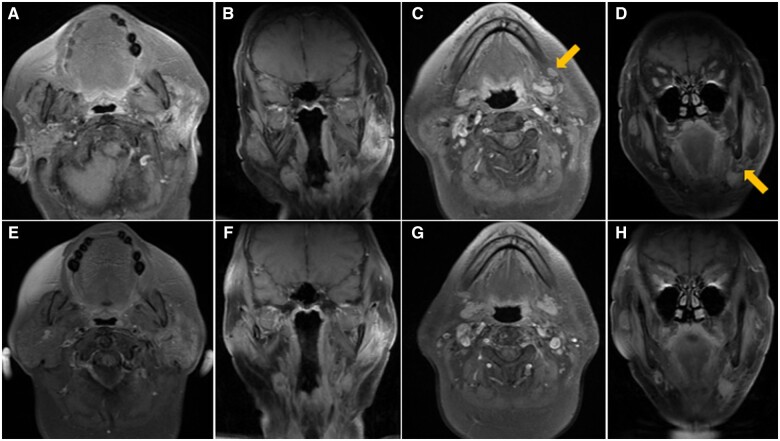

The authors present the case of a 59-year-old lady diagnosed with lymphoepithelial carcinoma (LEC) of the left parotid gland. The primary tumour was identified using contrast-enhanced CT, and diagnosis was confirmed via fine needle aspiration cytology and immunohistochemistry. Staging using fluorine-18 fluorodeoxyglucose PET CT revealed regional nodal metastases, while no distant metastasis was evident. Following radical radiotherapy, a favourable locoregional response was observed on MRI, yet the patient's plasma Epstein-Barr virus load continued to rise. Given her primary tumour's somatostatin receptor type 2 (SSTR2) positivity, gallium-68 DOTA-[Tyr3] octreotate PET CT (68Ga-DOTATATE PET CT) was performed, revealing multiple distant metastases with DOTATATE avidity. Despite attempts at palliative chemotherapy and immunotherapy, disease progression led to the decision for the best supportive care. The unique presentation of metastatic LEC on 68Ga-DOTATATE PET CT suggests a potential role for SSTR2-targeted imaging in diagnosis and management.